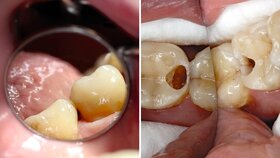

Für die Praxis bedeuten diese Fakten, dass bei Seniorinnen und Senioren ein verstärktes Augenmerk auf Präventivmaßnahmen unter Berücksichtigung der Zunahme freiliegenden Wurzeldentins gerichtet werden muss. Zudem werden vermehrt Austauschrestaurationen erforderlich werden. Da bedingt durch den Abbau des parodontalen Stützgewebes Wurzelkaries-Läsionen zunehmen werden, müssen neue Restaurationskonzepte Eingang in die Praxis finden. Dabei sollte im hohen Alter und bei Patienten mit schlechtem Allgemeinzustand die Erneuerung von Restaurationen mit Augenmaß vorgenommen werden. Vermutlich wird also die Anzahl von Reparaturmaßnahmen zunehmen.

Einer verbesserten Parodontaldiagnostik mit einer Ausweitung der nicht chirurgischen Parodontaltherapie ist bereits mit den neuen Paro-Richtlinien der Weg geebnet worden. Notwendig wird aber auch eine verbesserte Diagnostik und Therapie von nicht-kariösen Zahnhartsubstanzdefekten. Endodontische Maßnahmen werden vermutlich bei Patienten im höheren Lebensalter komplizierter werden und es wird wahrscheinlich eine verstärkte Nachfrage nach Implantaten geben. Gleichzeitig bedeutet dies jedoch auch, dass neben den üblichen Zahnextraktionen vermehrt Implantatentfernungen erforderlich sein werden.